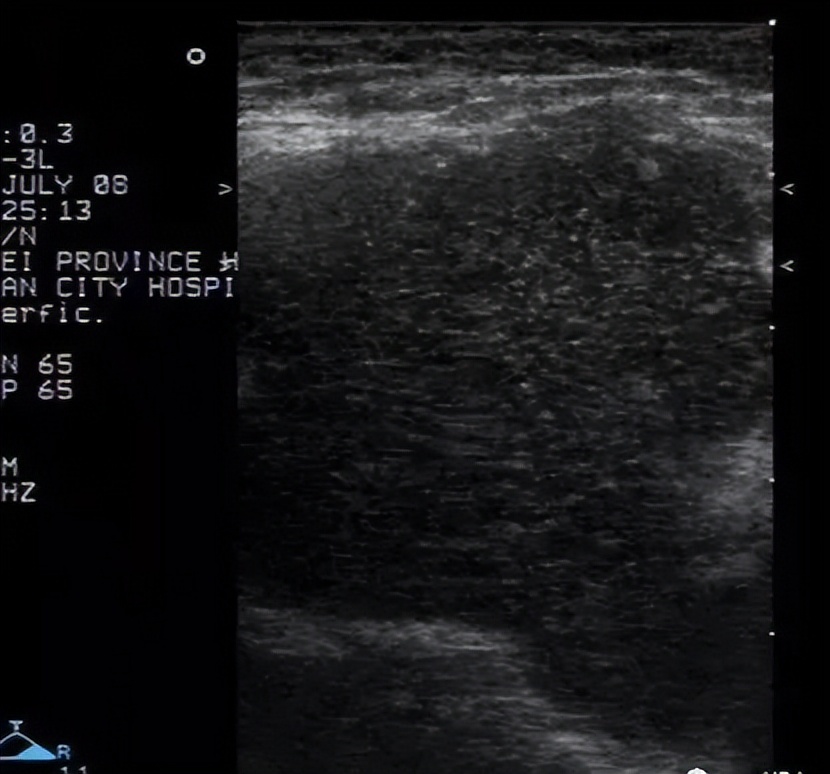

3. 副乳:发生率为1%~5% ,发生部位常见于腋窝或胸前部,多对称分布。可随着月经来潮而发生周期性的变化,妊娠期增大较明显,哺乳期可有泌乳。

超声表现:一般在表浅的皮下探及乳腺样组织,位置较表浅,呈薄片状。

小的副乳应和脂肪堆积鉴别

脂肪堆积表现为腋下皮下脂肪局部增厚,边界不清,与脂肪组织相连,按脂肪组织有规律排列;小副乳不按脂肪组织有规律排列,回声类似腺体组织回声。